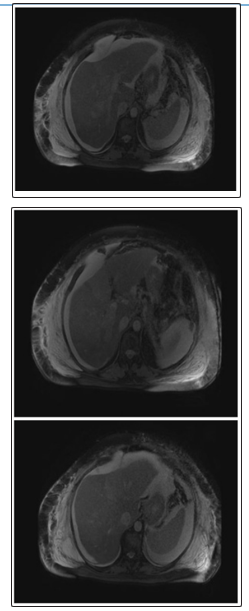

Magnetic resonance venography (MRV) which showed occlusion of right intrahepatic portal vein:

Fine needle aspiration biopsy with reticulin stain demonstrated a thickened hepatocellular plate consistent with trabecular hepatocellular carcinoma. According to the Barcelona-Clínic Liver Cancer (BCLC) staging system, the patient was classified as Child- Pugh Class C. Based on the Eastern Cooperative Oncology Group (ECOG) Performance status, she had a score of 3 points and was thus staged end-stage HCC, with expected survival less than 3 months. No therapeutic interventions were offered by the time diagnosis was established as the patient’s functional status had declined significantly and the disease was too advanced for possible improvement in life expectancy.